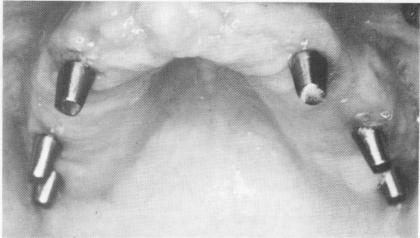

Grooves the same mesiodistal length as their corresponding blades were made in the desired areas of the ridge about 6 mm. deep. The blades were set in their grooves (Fig. 11-150) and tapped in until their shoulders were below the bony ridge (Fig. 11-151). The tissue was then completely closed with surgical ties (Fig. 11-152) . The palateless temporary denture was adjusted, lined with Hydrocast,* and fitted over

Fig. 11-152. Tissues were sutured over the implants.

Fig. 11-153. The healed tissues 2 weeks postoperatively.